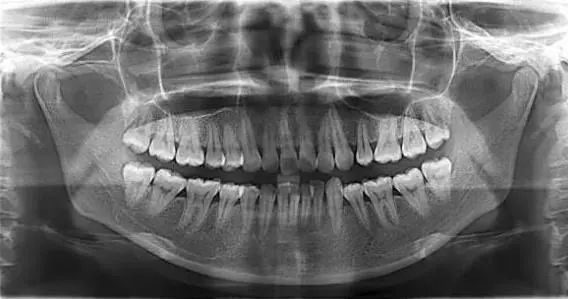

-韩国怡友vatech全景片-

用全景机为牙齿拍一张全景片,可将口腔内部所有细节清晰显现在医生眼前,每颗牙齿的问题、骨骼的排列和轮廓,甚至连每一根血管和神经都清晰的毫发毕现,如同GPS定位系统一般,一切尽在医生掌握中。

这样极大加强了手术安全性、提升手术效果。